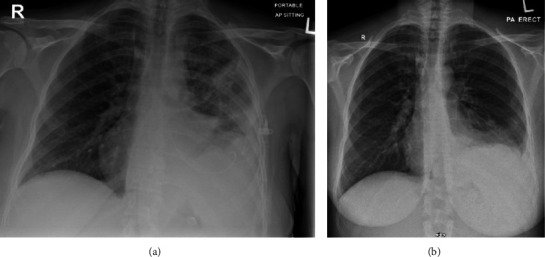

Chylothorax is accumulation of chyle in pleural space. Causes include traumatic, such as after esophagectomy, and nontraumatic, most commonly malignancy. Lymphoma usually presents as asymptomatic lymphadenopathy, and chylothorax tends to occur late in disease course. Chylothorax as initial presentation of lymphoma is rare with only case reports. We present a case of 43-year-old female who presented with dyspnea only with no B symptoms and found to have left-sided chylothorax, and was later diagnosed to have stage IV follicular lymphoma. This case highlights an atypical presentation of follicular lymphoma, to help physicians to reach diagnosis earlier in similar cases.